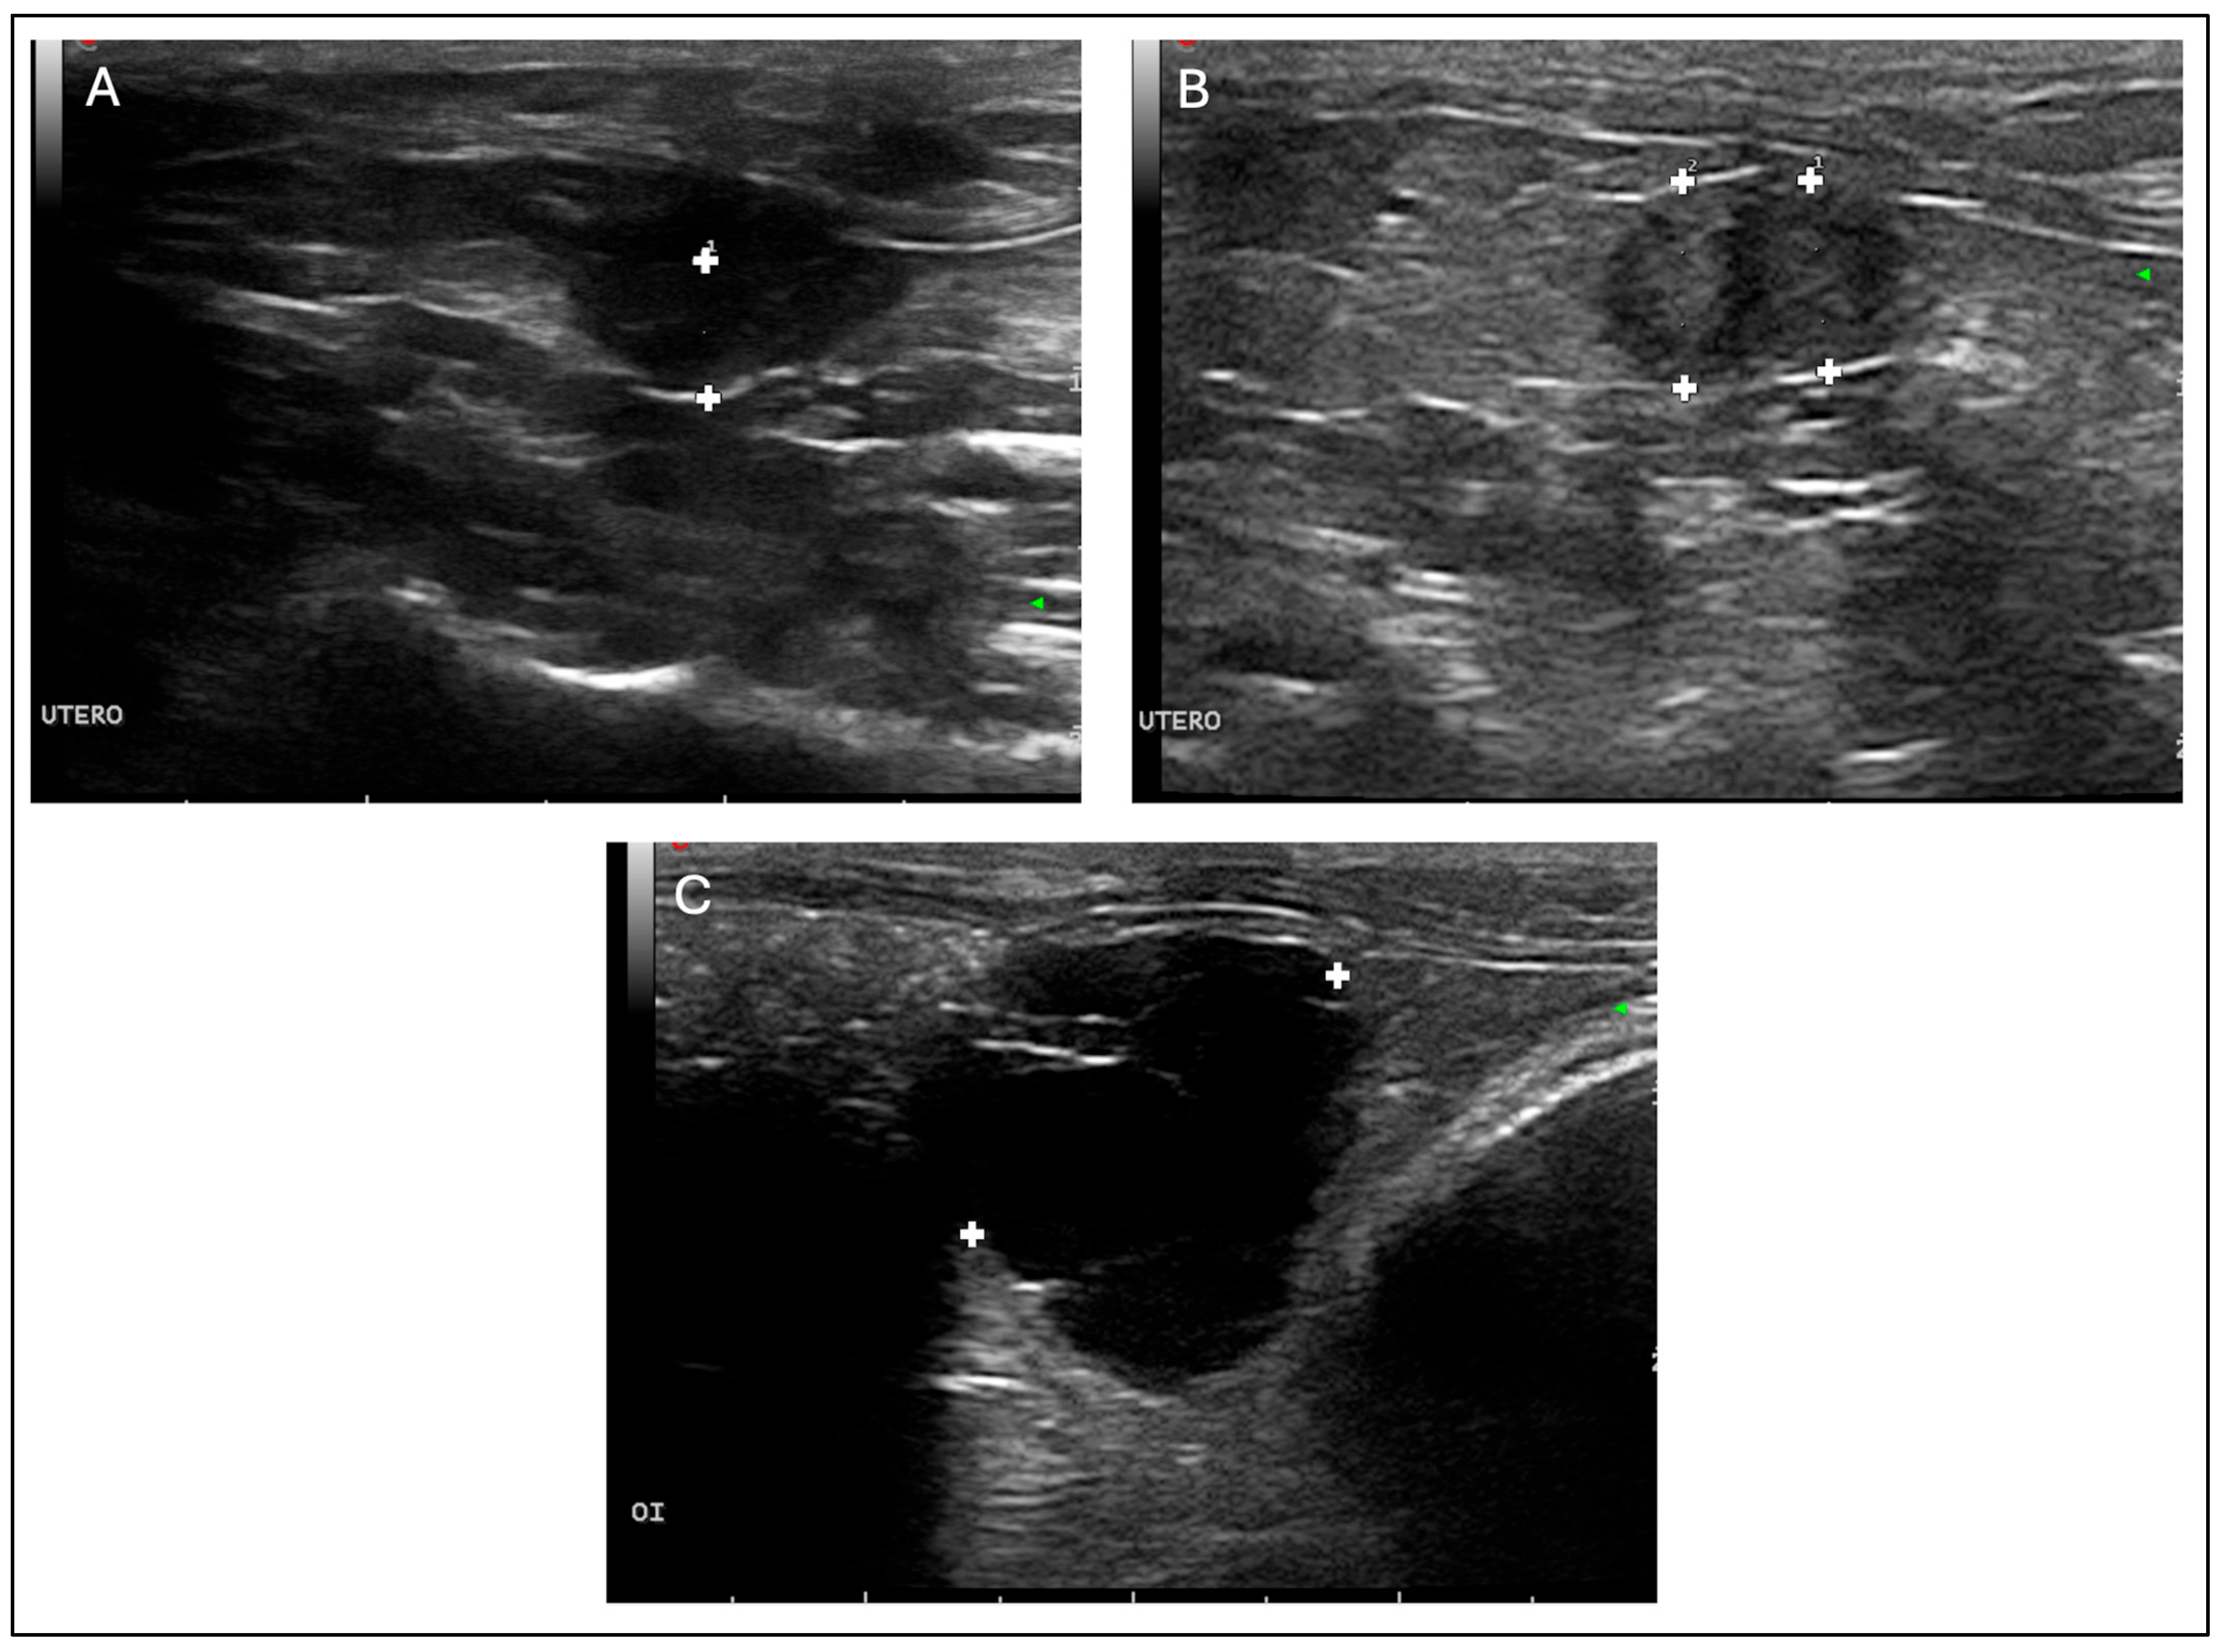

An abdominal ultrasound examination was performed under sedation (to minimise stress), using medetomidine (0.25 mg/Kg IM, Domtor, Esteve, Barcelona, Spain), and buprenorphine (0.03 mg/Kg IM, Buprex, RB Pharmaceuticals, Berkshire, UK) using a 12 MHz linear probe (Esaote MyLab LA523, United Medical Instruments, Inc., CA, USA). No free fluid was found. The ovaries were notably enlarged, containing multiple rounds, thin-walled anechoic cavities with smooth, well-defined contours and close apposition between adjacent cysts, showing marked posterior acoustic enhancement, consistent with clear fluid content (Figure 1C). The cystic structures lacked internal septations or suspended echogenic material, and no peripheral vascularisation was detected, suggestive of non-functional cysts of rete ovarii origin.

Figure 1.

Abdominal ultrasonographic findings in a 2-year-old female guinea pig (Cavia porcellus). Sagittal section of the uterus body thickened (diameter: 0.37 cm) (A); cross-sectional view of both uterine horns thickened (left horn diameter: 0.57 cm, right horn diameter: 0.54 cm) (B); cross-sectional image of the left ovarian cyst (diameter: 2.3 cm) (C). Images were obtained using a linear probe (Esaote MyLab LA523, 12 MHz).

The uterine body and horns appeared enlarged, with thickened and irregular walls. Multiple round anechoic cavities were identified both within the uterine lumen and embedded in the endometrium. These cystic spaces had sharply delineated margins, thin walls, and homogeneously anechoic content. The uterine wall displayed a heterogeneous echotexture, characterised by increased echogenicity of the superficial endometrium and partial loss of normal stratification, findings indicative of chronic inflammatory changes or cystic endometrial hyperplasia (Figure 1A,B). No solid masses or evidence of rupture were observed. An OVH was therefore scheduled for the following day.

Ovarian cysts are the most common reproductive disorder in adult female guinea pigs [1,6], and distinguishing functional (follicular) from non-functional rete ovarii cysts is clinically relevant because of their differing endocrine effects [4,7]. Functional cysts are oestrogen-secreting and may induce alopecia, behavioural changes, and uterine alterations, whereas rete ovarii cysts are non-hormonal and typically asymptomatic [6,10,17]. Ultrasonography is useful for this distinction: follicular cysts often show heterogeneous or slightly echogenic fluid, occasional internal septa, or peripheral vascularisation, reflecting their endocrine activity. In contrast, rete ovarii cysts characteristically appear as thin-walled, uniformly anechoic, avascular structures with pronounced posterior acoustic enhancement [6,10,13]. In this case, the presence of multiple smooth, anechoic, non-septated and avascular cysts strongly supported a diagnosis of non-functional rete ovarii cysts, later confirmed histologically. The coexistence of rete ovarii cysts and CEH has been reported only sporadically [10,13], and the limited number of well-illustrated cases restricts current understanding of their clinical interplay.

Ultrasonography is the diagnostic modality of choice for assessing the reproductive system of small exotic mammals, as it allows detailed evaluation of ovarian and uterine structures without the need for invasive procedures, is readily available in general practice, and avoids exposure to ionizing radiation [1,4,13]. In the present case, the ultrasound examination demonstrated the concurrent presence of multiple bilateral, thin-walled, anechoic cavities within the ovarian parenchyma, lacking septa or echogenic material, findings consistent with rete ovarii cysts. The uterine body and horns exhibited diffuse wall thickening and partial loss of mural stratification, with intramural and luminal anechoic areas compatible with CEH. The diameter of both uterine horns (0.54 and 0.57 cm) exceeded the physiological value reported by Laik-Schandelmaier et al. (2017) [7], who described an average of 3 mm in healthy females, thereby supporting the suspicion of an inflammatory or hyperplastic process. The published literature provides limited simultaneous imaging documentation of ovarian and uterine abnormalities. Most reports include only textual descriptions or macroscopic photographs, without comprehensive ultrasonographic correlation of both structures [6,10]. Even in a surgical series of 41 flank ovariohysterectomies [18], ultrasonography is mentioned as a preoperative diagnostic aid but without representative images of affected uterus and ovaries. Therefore, the present case provides comprehensive and high-quality visual documentation, contributing to the recognition of sonographic patterns compatible with rete ovarii cysts and CEH in guinea pigs.